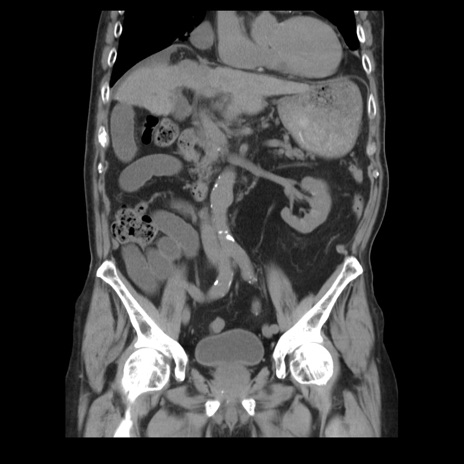

横断像

【症例】70歳代男性

【主訴】腹痛

【現病歴】肝硬変・肝細胞癌にてかかりつけの方。約9時間前に食後より腹痛出現。症状が徐々に増悪し、嘔吐出現したため来院。

【既往歴】肝硬変、肝細胞癌(RFA、TACE後)

【身体所見】意識清明、表情苦悶様、BT 36℃、BP 129/78mmHg、P 88bpm、SpO2 97%(RA)、右上腹部から心窩部にかけて圧痛あり、反跳痛なし、筋性防御あり。

【データ】WBC 5800、CRP 0.16